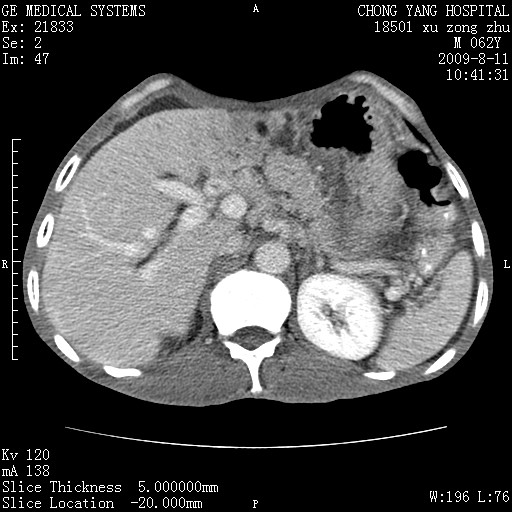

以下是引用杀毒软件在2009-8-11 16:35:00的发言:[br]肝内胆管扩张局限于左叶,胆管内有结石伴肝外胆管结石,胆管壁增厚呈弥漫性并发腹腔积液,胰腺边界模糊。[br][br]考虑---胆总管及肝内胆管结石继发胆管炎及胰腺炎,左肾下极囊肿,腹水。

以下是引用zjzjr在2009-8-11 17:35:00的发言:[br]肝内胆管扩张局限于左叶,胆管内有结石伴肝外胆管结石,胆管壁增厚呈弥漫性并发腹腔积液。[br][br]考虑---胆总管及肝内胆管结石继发胆管炎,左肾下极囊肿,腹水。